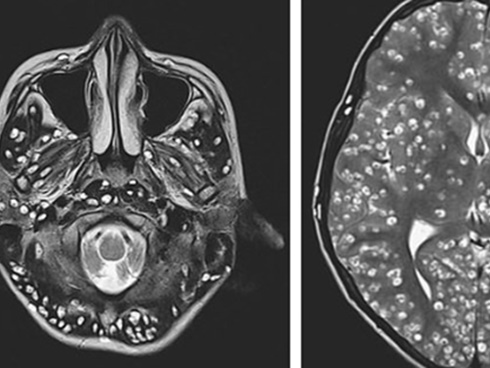

Sán lợn - ấu trùng sán lợn (Cysticercosis)

Bệnh lây do quá trình ăn uống thức ăn (thịt lợn) hoặc rau sống, hoa quả có chứa trứng của sán lợn sẽ nhanh chóng phát triển thành ấu trùng sán lợn. Ấu trùng ký sinh ở tại cơ quan nào sẽ có biểu hiện lâm sàng.

Ở lợn thì biểu hiện thường ở cơ, xương nhưng ở con người, ấu trùng sán lợn thường ký sinh tại hệ thần kinh, đặc biệt là não hoặc tủy sống, mắt.

Người bệnh có biểu hiện đau đớn toàn thân. Đau đầu âm ỉ, dữ dội kèm buồn nôn, nôn do khối choán chỗ (nang sán) của ấu trùng sán tạo ra trong não, liệt thần kinh khu trú… khi nang sán bị ly giải, vôi hóa (sẹo thần kinh) có thể xuất hiện các cơn động kinh cục bộ hoặc toàn thân.